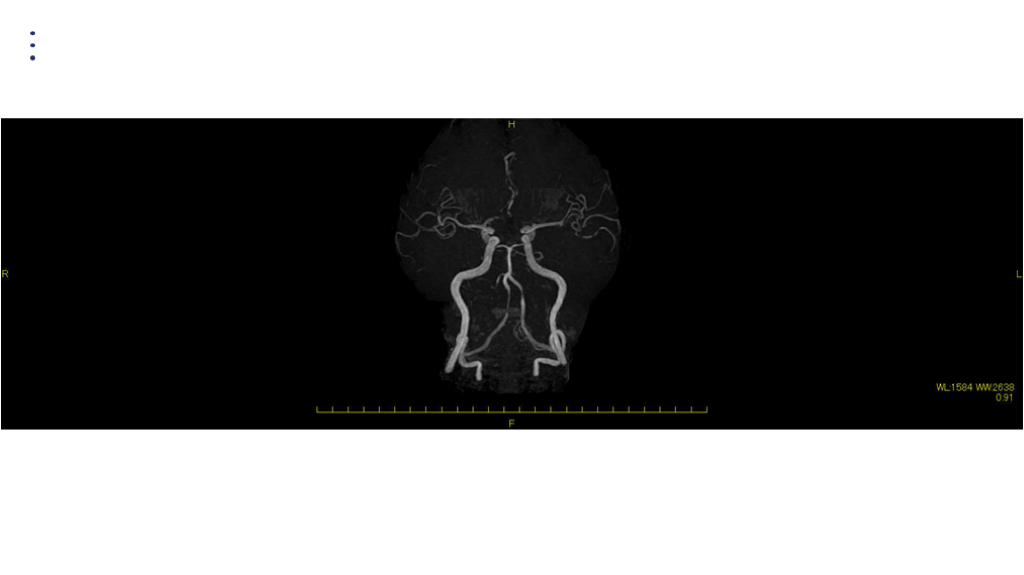

MRA DAY2

画像 所見 DAY 14 MRA 悪化